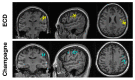

Magnetoencephalography (MEG) is increasingly used for presurgical planning in people with medically refractory focal epilepsy. Localization of interictal epileptiform activity, a surrogate for the seizure onset zone whose removal may prevent seizures, is challenging and depends on the use of multiple complementary techniques. Accurate and reliable localization of epileptiform activity from spontaneous MEG data has been an elusive goal. One approach toward this goal is to use a novel Bayesian inference algorithm-the Champagne algorithm with noise learning-which has shown tremendous success in source reconstruction, especially for focal brain sources. In this study, we localized sources of manually identified MEG spikes using the Champagne algorithm in a cohort of 16 patients with medically refractory epilepsy collected in two consecutive series. To evaluate the reliability of this approach, we compared the performance to equivalent current dipole (ECD) modeling, a conventional source localization technique that is commonly used in clinical practice. Results suggest that Champagne may be a robust, automated, alternative to manual parametric dipole fitting methods for localization of interictal MEG spikes, in addition to its previously described clinical and research applications.